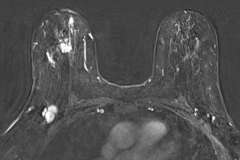

MRI